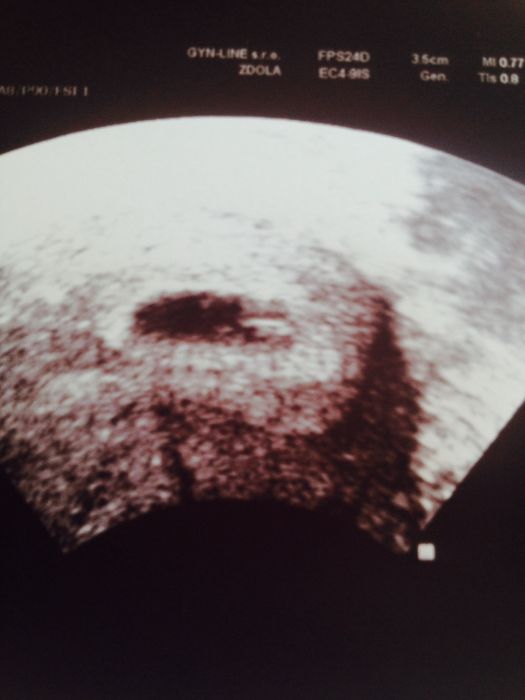

Holky tak vam ukazuju my 6mm mimusko :)) vidíte ho? Úplne vpravo v te černé bublince ;) jo a jeste mi doktor rikal, ze je tam jen jeden plod ;)) naštěstí ;))

Jé, boží! I když ten utz moc kvalitka není, tak miminko rozpoznávám